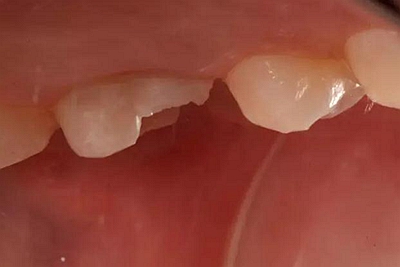

下面為一例纖維樁全冠修復(fù)后,纖維樁斷裂的病例,同樣實(shí)行了冠延長(zhǎng)手術(shù)。

患者女性,55歲,3年前B3纖維樁+鑄瓷全冠修復(fù),一周前牙冠折斷,就診后,發(fā)現(xiàn)纖維樁根管口處折斷,周圍牙齦增生,建議患者行冠延長(zhǎng)手術(shù)。首先去除斷端的纖維樁。拍片示牙根長(zhǎng)度充足。于是開始冠延長(zhǎng)手術(shù)。

因?yàn)槭乔把?,故該患者將?lái)修復(fù)體邊緣必須為齦下,所以3個(gè)月后再行修復(fù)。以下為手術(shù)前照片。